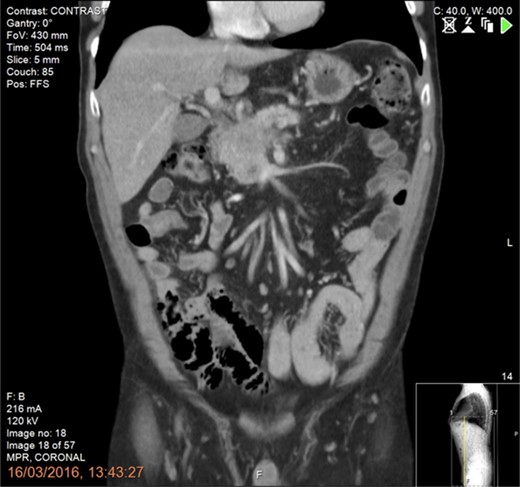

Final histology, using the Leeds protocol and the recommendations of the Royal College of Pathologists, revealed a ypT3N0M0 (UICC TNM Seventh Edition) moderately differentiated pancreatic ductal adenocarcinoma [7] (Fig. 4a and b). All resection margins including the posterior margin and the SMA/ SMV bed were negative (Fig. 5a and b). None of the 23 lymph nodes resected was involved by tumour.

(a and b) Pancreaticoduodenectomy specimen sliced in an axial plane, according to the Leeds Pathology Protocol, providing good visualization of the tumour and its relationship to key anatomical structures and the anterior, posterior and superior mesenteric vein groove surfaces. (a) Demonstrates an area of haemorrhage/necrosis due to IRE needles extending to the SMV bed (arrow) and (b) shows the SMV (arrrowhead) and the SMA groove (arrow).